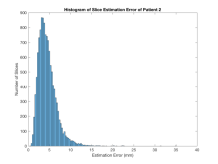

We have tested our approach on 85 randomly selected and accurately segmented healthy adult brains, on a real-world use case scenario with 34 roughly delineated fetal brain MRI scans and on 60 low-dose thorax CT scans with no organ specific segmentation. SVRNet’s average prediction error for these datasets is respectively 5.61.07mm, 7.74.80mm, and 5.92.43mm. We evaluate 3D reconstruction performance using the Peak Signal-to-Noise Ratio (PSNR) and prediction error as average distance in mm between ground truth locations and predicted locations , i.e., .

Exp. 2: Fetal brain data is used to test the robustness of our approach under real conditions. Fetuses younger than 30 weeks very often move a lot during examination. Fast MRI sequences allow artifact free acquisition of individual slices but motion between slices corrupts consistent 3D information. Fig. 3 shows that our method is able to accurately predict also under these conditions. For this experiment we use from three orthogonally overlapping stacks of ssFSE slices covering the fetal brain with approximately 20-30 slices each. We are ignoring the stack transformations relative to the scanner and treat each individually. For , 28 clinically approved motion compensated brain reconstructions are resampled into a volume with spacing. A density of 500 unique sampling normals has been chosen via the Fibonacci sphere sampling method with 25 sampling planes evenly spaced between -25 to +25 on the Z-axis. This gives a plane spacing of 2mm, sampling only the middle portion of the fetal brain. Training took approximately 10hrs for 30 epochs. Prediction, i.e., the forward pass through the network, takes approx. 12 ms/slice.